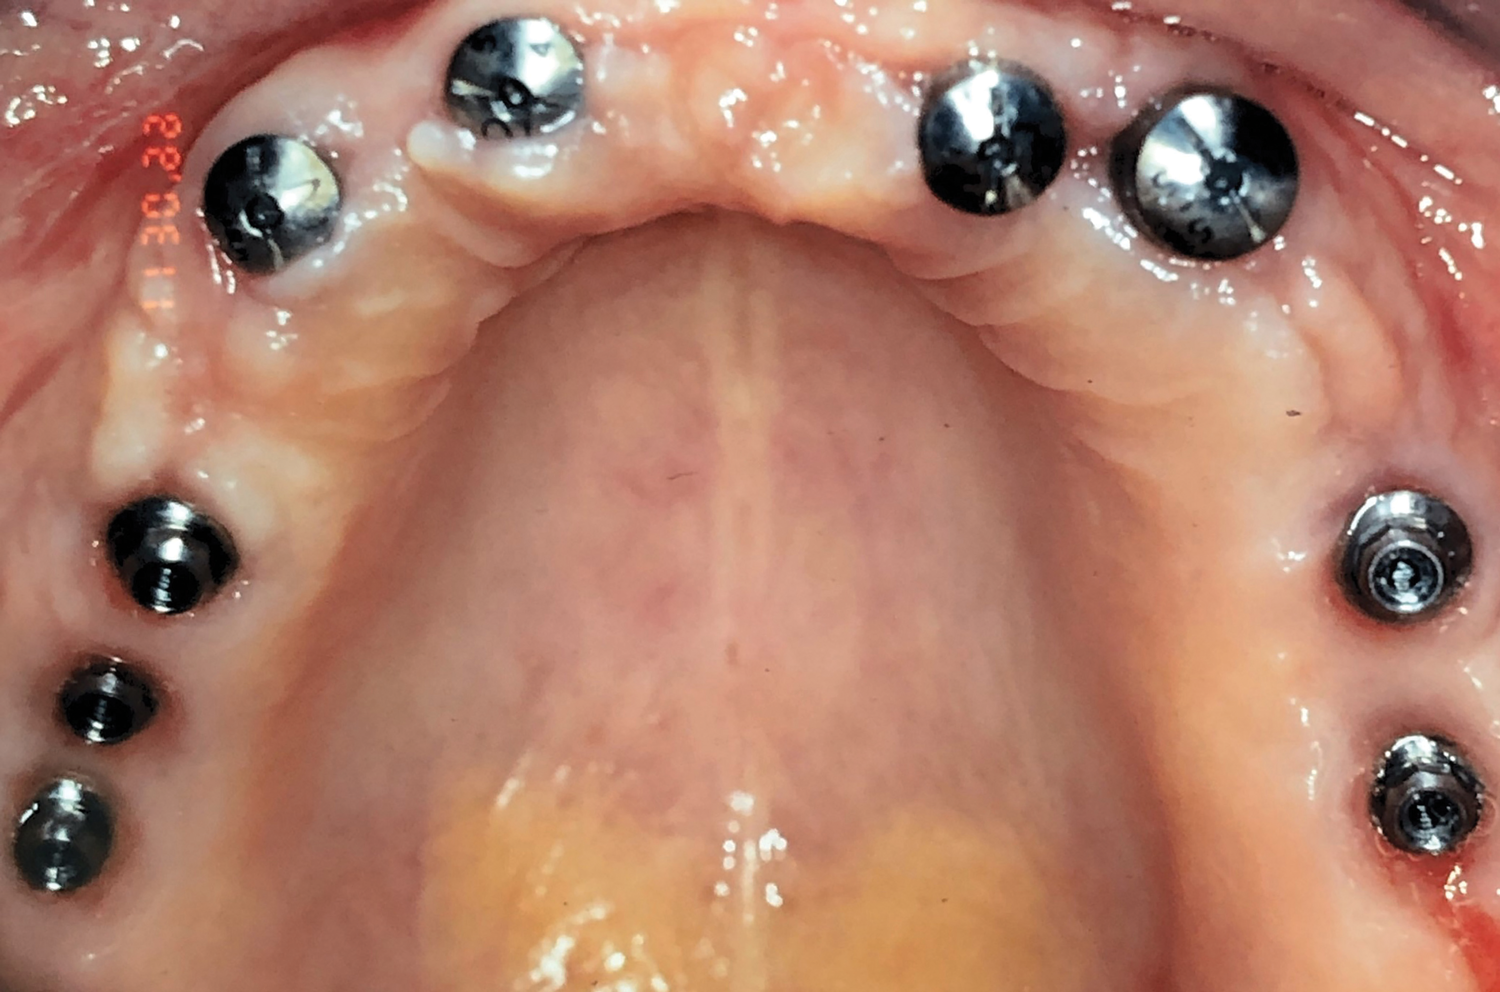

Fig 1. Initial occlusal view of maxillary arch.

Figure 1

Fig 3. Maxillary arch after placement of TIs.

Figure 3